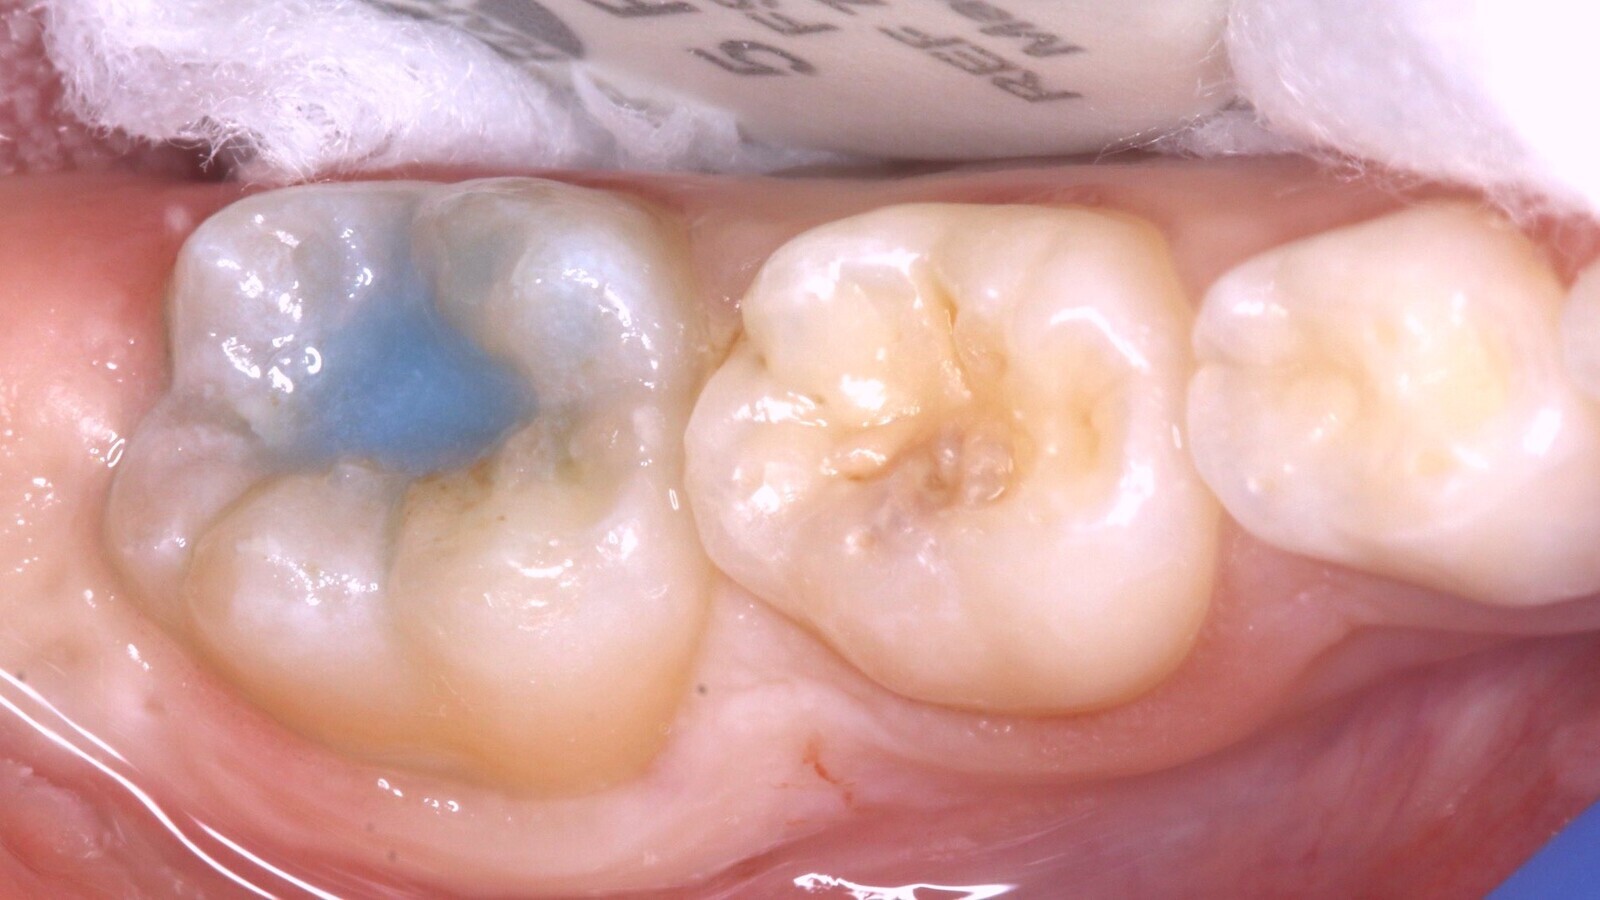

Imágenes inicial (A), radiográfica (B) y final (C) del diente 46 de una paciente de 7 años con sensibilidad dentinaria, que se restauró utilizando el material estético de fraguado rápido EQUIA Forte fil, y la resina compuesta everX Flow. Estos materiales utilizan la nueva tecnología de vidrio híbrido y actúan de forma sinérgica para formar un material más fuerte de colocación en bloque.

Al realizar el examen clínico, el diente 46 presenta una sombra subyacente en la dentina apreciada desde oclusal (Fig. 1), que al manejar el sistema internacional de detección y valoración de caries dental se considera una lesión ICDAS 4 (sombra subyacente en la dentina con esmalte aparentemente intacto). El examen radiográfico, con una exposición de aleta de mordida, evidencia una imagen radiolúcida que alcanza al tercio medio de la dentina (Fig. 2).

Por la severidad de la lesión, sin una cavidad evidente, se decide realizar una remoción de esmalte con alta rotación utilizando fresas diamantadas con la finalidad de acceder a la dentina cariada con instrumentos manuales, complementados con un agente enzimático a base de papaína (Papacarie Duo, Formula & Ação) (Fig. 3).

Antes de proceder con la limpieza de la cavidad, se toma una impresión de la anatomía con un material de barrera gingival (Gingival Barrier, SDI Ltd.) fijado en un micro-aplicador (Fig. 4), de forma que se pueda copiar la anatomía existente mediante la técnica del estampado oclusal (Fig. 5). Tras realizar la apertura de la cavidad (Fig. 6) se inicia la remoción selectiva del tejido cariado con una estrategia químico-mecánica (Fig. 7) hasta llegar a DENTINA FIRME en la base y dura en la periferia de la cavidad (Fig. 8) bajo aislamiento relativo utilizando Optragate (Ivoclar Vivadent) y rollos de algodón, se procede a aplicar el material restaurador EQUIA Forte fil (Fig. 9).